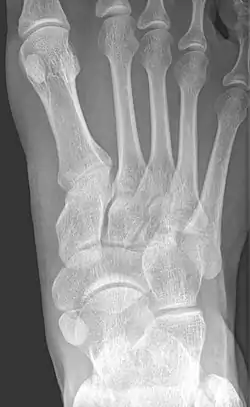

From left to right: Type 1, 2 and 3